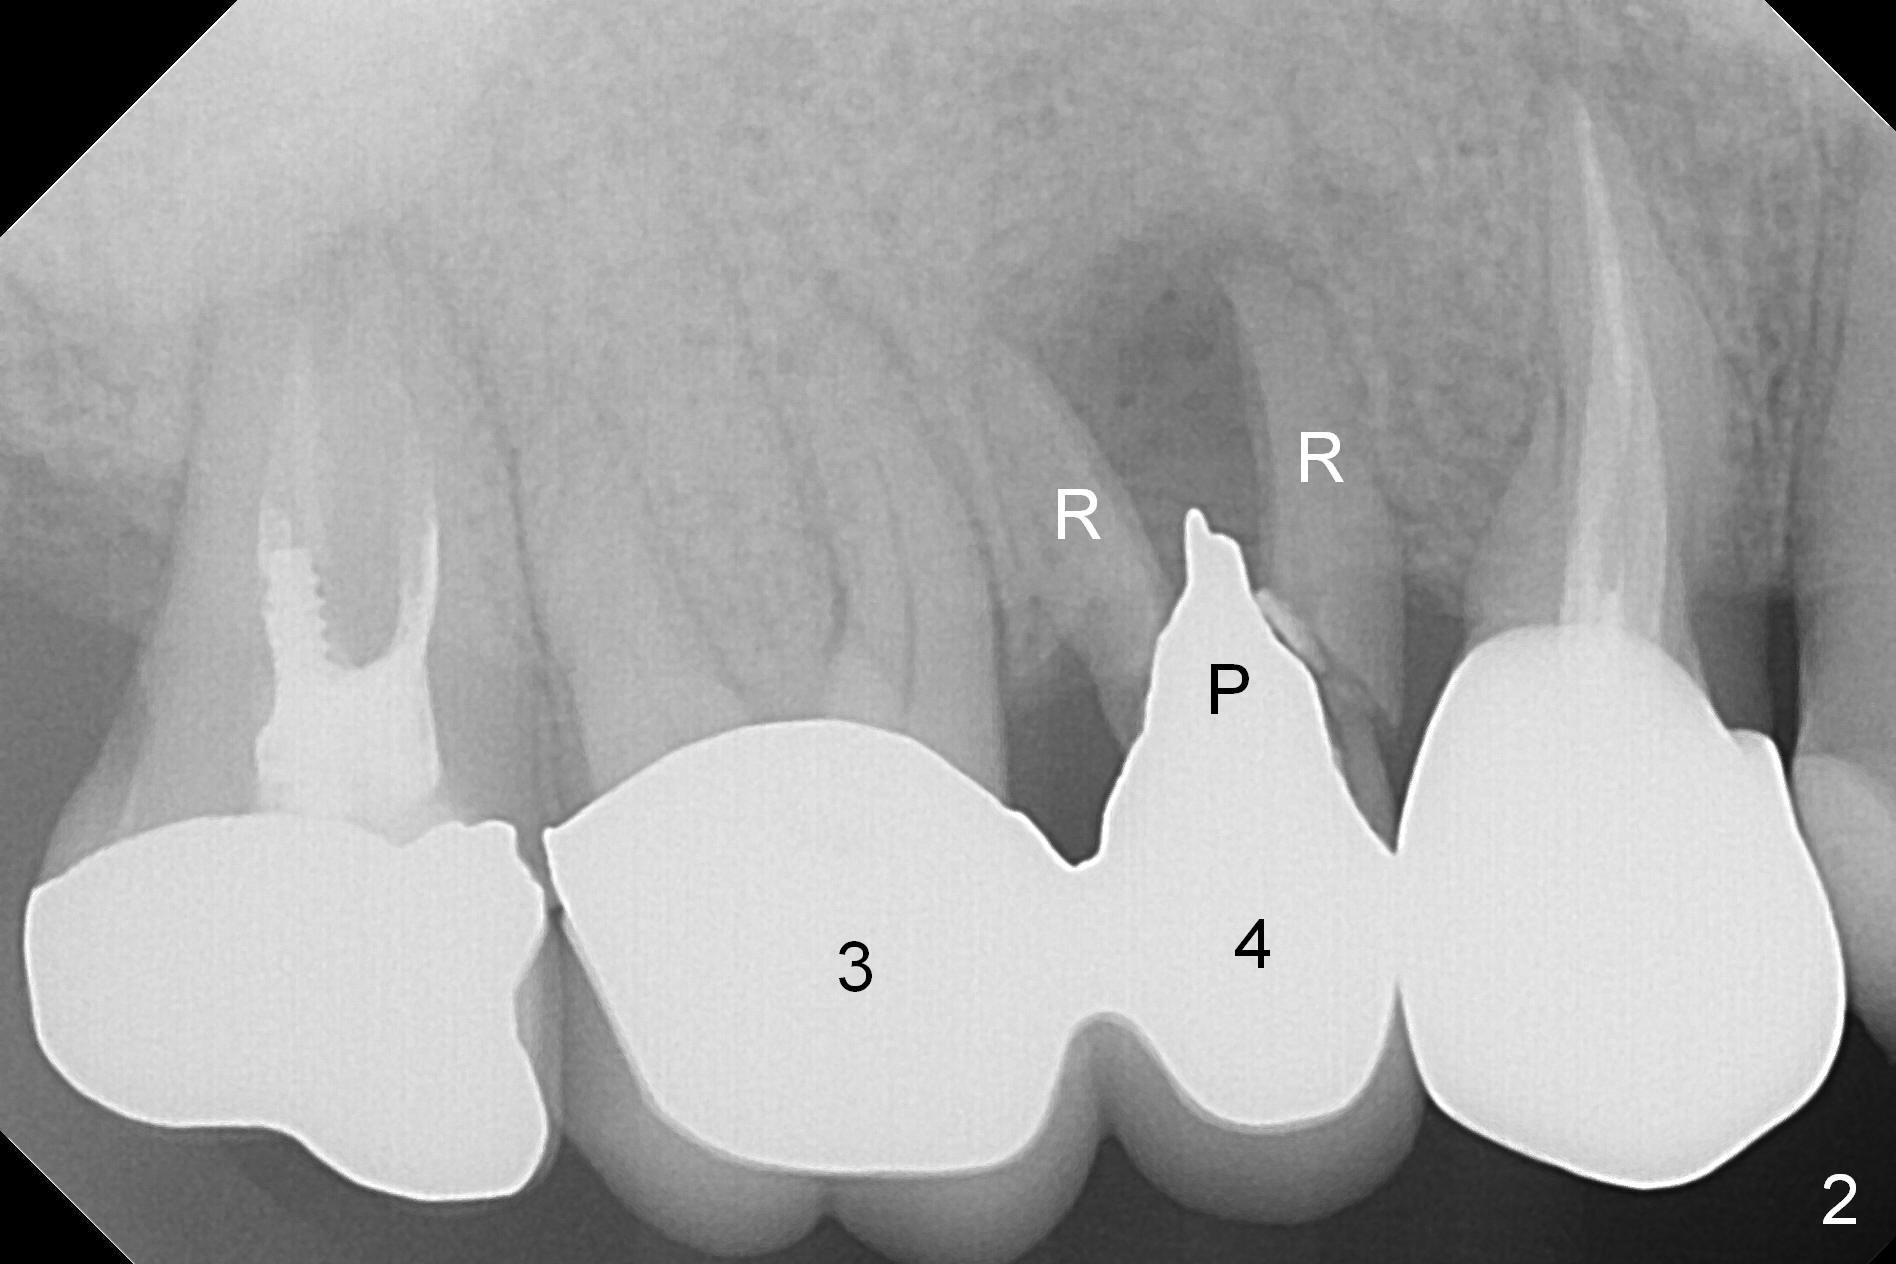

A 42-year-old man returns with chief complaint of chipped tooth at #3. Crowns at #3 and 4 are splinted (Fig.1). The tooth #4 is discolored (^). X-ray exam shows post (P) -induced Root (R) split with severe bone loss at #4 (Fig.2). To decrease periimplantitis, use an implant as narrow as possible (4 mm) and as long as apical bone allows (13 mm, IBS, Fig.3). Section the retainer at #3 and remove the tooth #4 (Metronidazole). Prepare PVS impression to record socket morphology. Magic Expanders are to be applied for osteotomy and sinus lift if possible. Finally fabricate splinted provisional at #3 and 4.